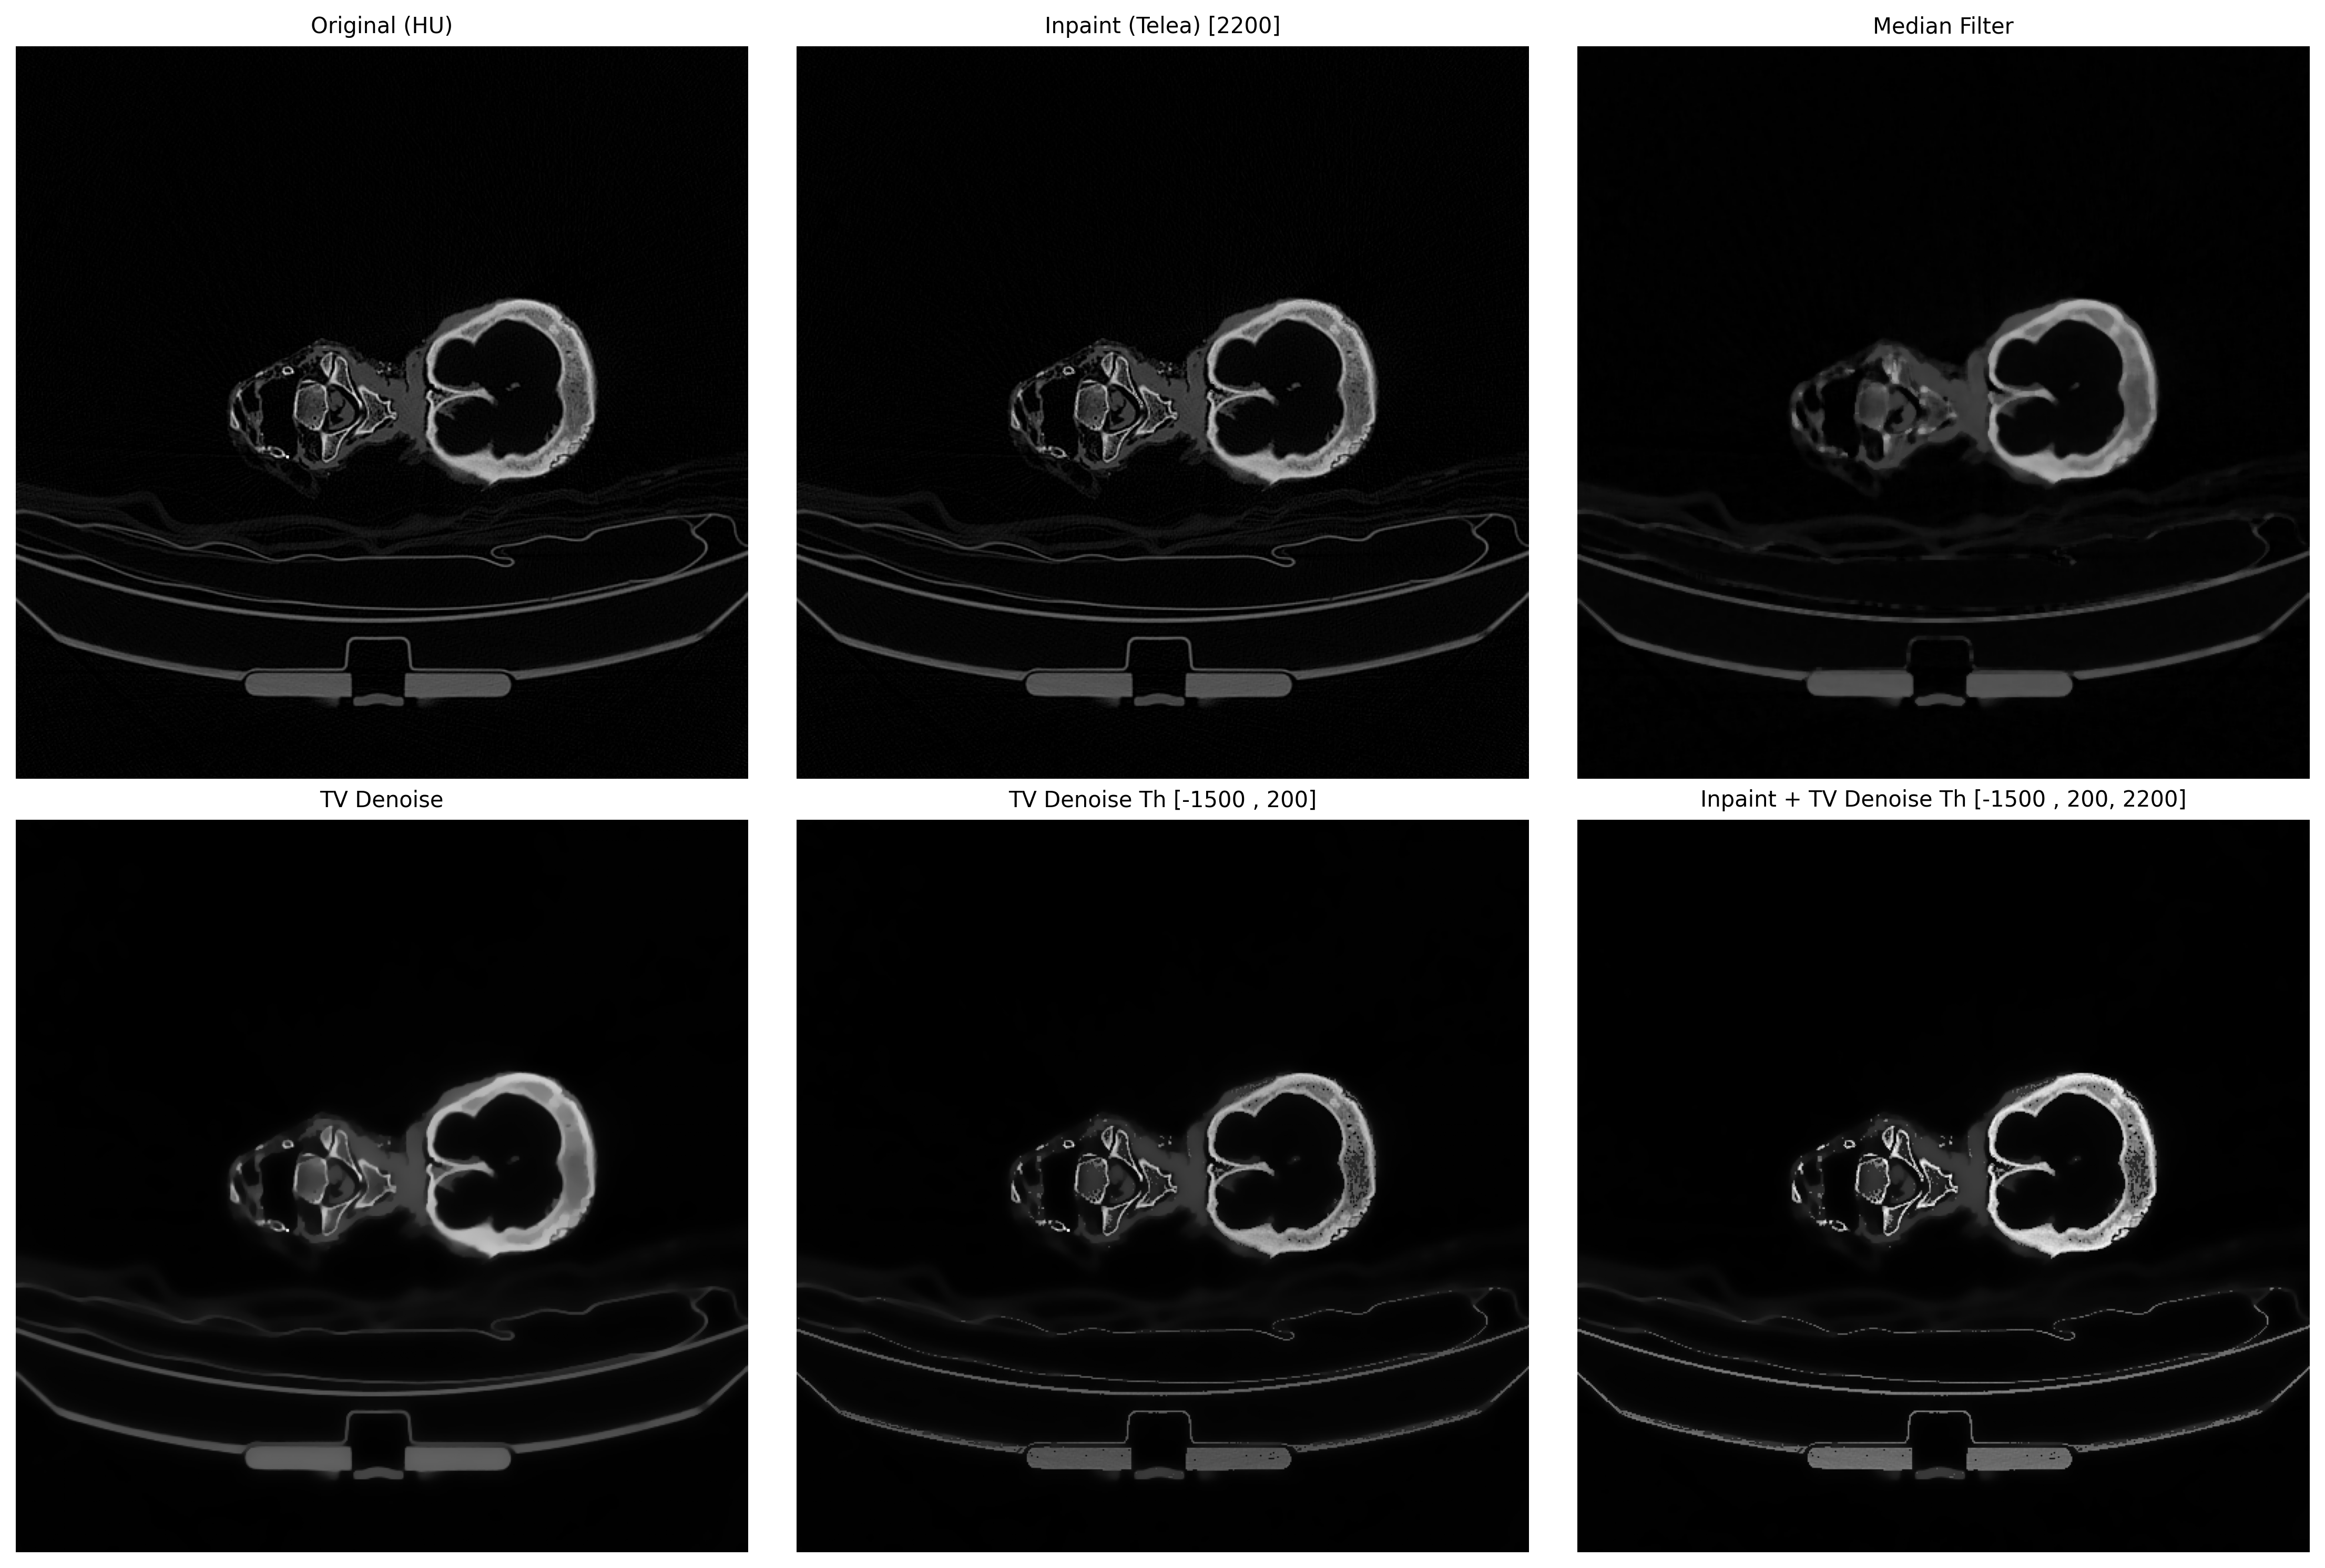

# 5. 汇总图

def create_summary(ct_hu, artifact, results, file_name):

fig, axes = plt.subplots(2, 3, figsize=(15, 10)) # 两行三列

axes = axes.ravel()

def show(i, img, title):

axes[i].imshow(img, cmap='gray', vmin=0, vmax=255)

axes[i].set_title(title, fontsize=10)

axes[i].axis('off')

# 0 号位:原图

show(0, exposure.rescale_intensity(ct_hu, out_range=(0, 255)),

"Original (HU)")

# 1 开始放 results

for idx, (name, img) in enumerate(results, start=1):

show(idx, img, name)

# 隐藏剩余空白子图

for j in range(len(results) + 1, 6):

axes[j].axis('off')

plt.tight_layout()

plt.savefig(f"metal_artifact_summary_{file_name}.png", dpi=300, bbox_inches='tight')

plt.show()

results = [

("Inpaint (Telea) [{}]".format(threshold), inpaint_opencv(ct_hu, mask)),

("Median Filter", median_filter(ct_hu)),

("TV Denoise", denoise_tv(ct_hu)),

("TV Denoise Th [{} , {}]".format(hu_min, hu_max), denoise_tv_th(ct_hu, hu_min=hu_min, hu_max=hu_max)),

("Inpaint + TV Denoise Th [{} , {}, {}]".format(hu_min, hu_max, threshold), inpaint_denoise_tv_th(ct_hu, hu_min=hu_min, hu_max=hu_max, threshold=threshold)),

]

create_summary(ct_hu, ct_hu, results, file_name)

Inpaint能去除金属,拖影使用TV Denoise。

其他案例,但需要更具直方图就行调整。